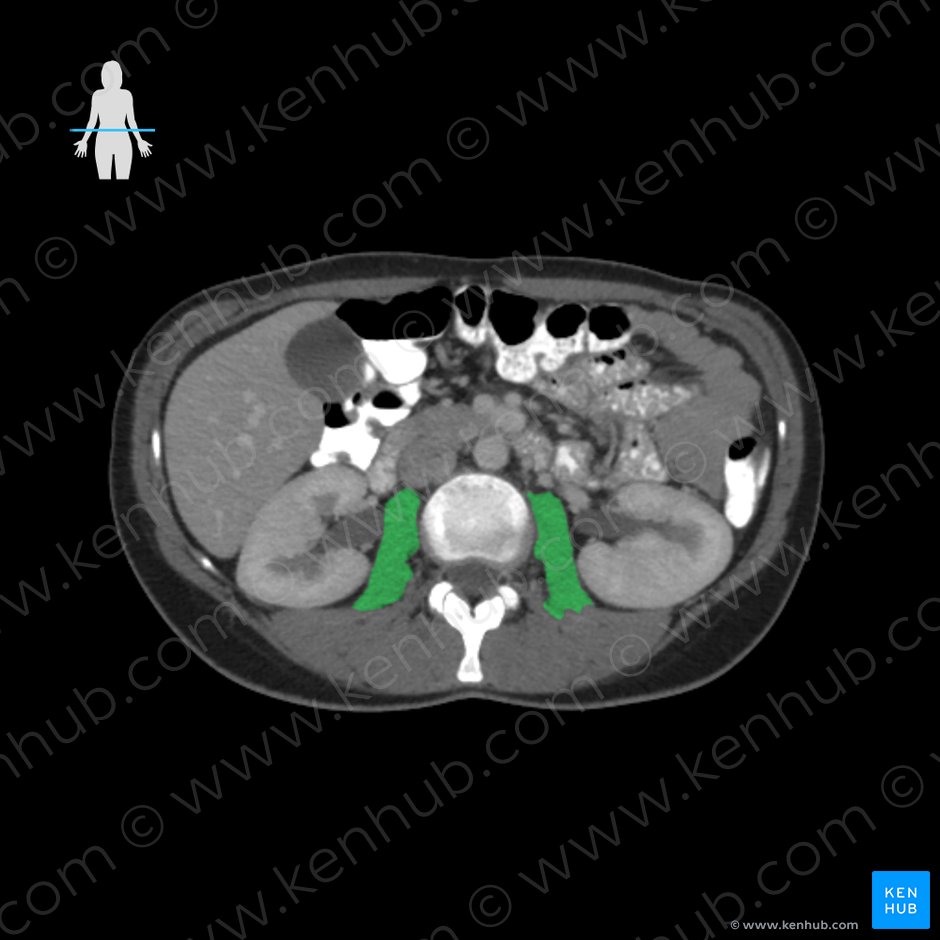

대요근 : 초록색, 장요근: 분홍색 (1) 대요근(psoas major)

origin: 전방부- L1-L5 척추체와 디스크의 옆면

후방부- T12-L4까지 횡돌기의 전면

(Vertebral bodies of T12-L4,

intervertebral discs between T12-L4,

transverse processes of L1-L5 vertebrae)

insertion: 대퇴골 소전자

(Lesser trochanter of femur as iliopsoas tendon)

Action: Hip joint- Flexion of the thigh/trunk,

lateral rotation of the thigh

Lateral flexion of the trunk(2) 장골근(illiacus)

장요근은 척추체에서 시작되는 대요근과

골반 안쪽에서 시작하는 장골근 두 근육이

하나로 합쳐져 대퇴골 소전자에 부착하는 근육입니다.